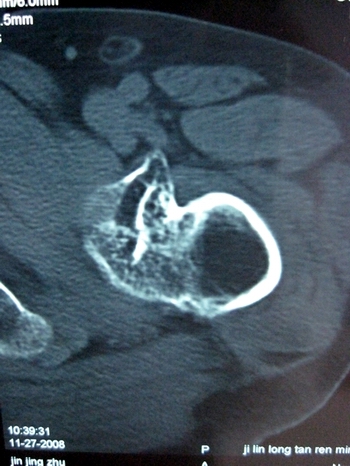

以下是引用lkc8963在2008-12-19 21:19:00的发言:[br]左?右?患侧大转子上移,股骨颈骨质浓杂,髋周见多发条片状骨化影,以小转子为著,多为陈旧性股骨颈骨折后改变并骨化性肌炎.请咨询既往史!